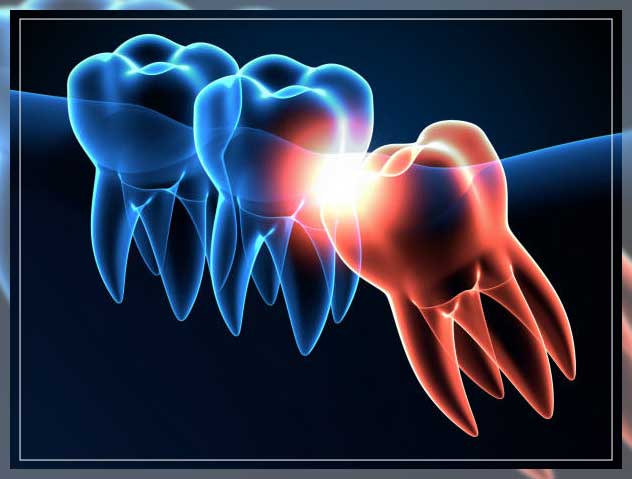

1. Impacted Tooth

You would be surprised to know that in most cases, your wisdom teeth do not pop out of your gum line in the way other teeth do. At times your wisdom teeth may grow crooked, pressing against or away from other teeth. Such a condition is commonly termed as “impacted”.

Some reviews say that more than 70 percent of all new third molar teeth are impacted. On the other hand, other reviews say that the number is less than 40 percent. This problem may lead to pain, infection, and inflammation.

One study confirmed that about 12 percent of impacted wisdom teeth include more severe symptoms. Impacted wisdom teeth often crowd other teeth, thus misaligning those teeth. The reason is that most wisdom teeth develop from the spongy tissue surrounding your jaw that does not have strong support. As a result, it creates most of these problems.